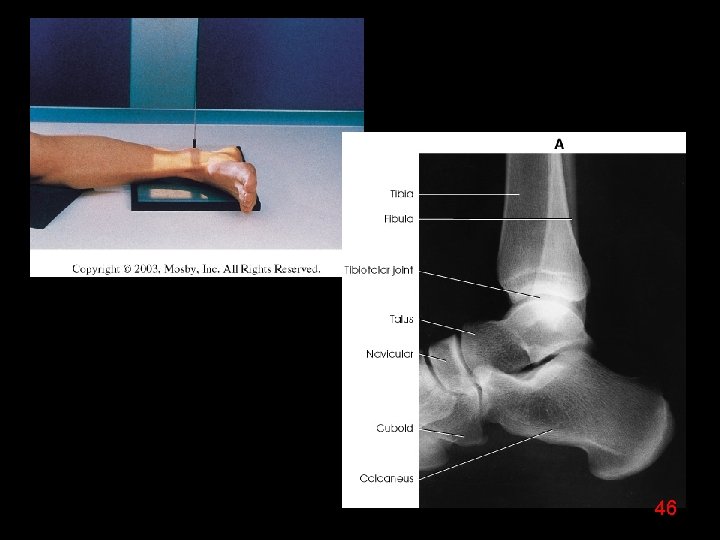

46

47